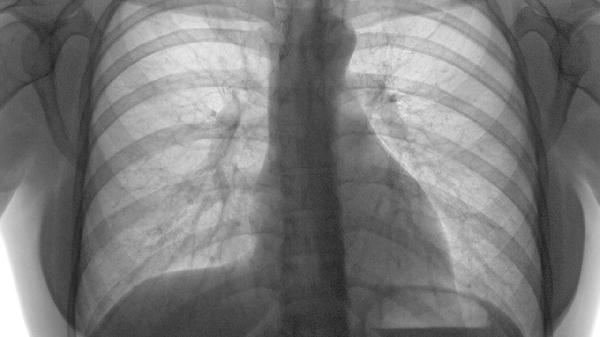

肺栓塞患者的药物治疗应基于病情严重程度和个体差异,常用药物包括抗凝药、溶栓药和支持治疗药物。治疗方案需由医生根据具体情况制定,以预防血栓扩大和复发。

1、抗凝药物是肺栓塞治疗的核心。低分子肝素、华法林和新型口服抗凝药如利伐沙班、达比加群是常用的选择。低分子肝素适合急性期治疗,起效快;华法林需定期监测凝血功能,调整剂量;新型口服抗凝药使用方便,无需频繁监测,但价格较高。抗凝治疗通常持续3-6个月,甚至更长时间。

2、溶栓药物适用于高危肺栓塞患者,血栓负荷大或伴有血流动力学不稳定。尿激酶、阿替普酶和瑞替普酶是常用药物。溶栓治疗能快速溶解血栓,但可能增加出血风险,因此需严格评估适应症和禁忌症。

3、支持治疗药物用于缓解症状和改善预后。氧疗是低氧血症患者的必要措施;利尿剂有助于减轻右心负荷;止痛药如阿司匹林可用于缓解胸痛。对于合并其他疾病的患者,还需根据情况调整用药。

肺栓塞患者的药物治疗需个体化,遵循定期监测和调整方案。同时,注意避免久坐、戒烟、控制体重和积极治疗原发病,有助于降低复发风险。